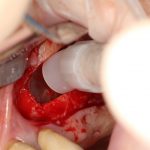

Ну хорошо. Швы сняли. Делаем разрез. Обрати внимание, что после всех проведенных операций у нас остается очень небольшой по ширине слой жевательной слизистой оболочки:

в связи с чем возникает резонный вопрос:

А нет ли здесь необходимости в дополнительной пластике десны?

Конечно, сейчас мы действуем значительно деликатнее. И не делаем такие разрезы без необходимости:

С другой стороны, если бы делали «как сейчас», ты не увидел бы ничего интересного.

Устанавливаем формирователи десневой манжеты. Сегодня я называю эту процедуру не менее важной, чем любой другой этап имплантологического лечения:

И швы. Просто швы. Никаких дополнительных процедур.